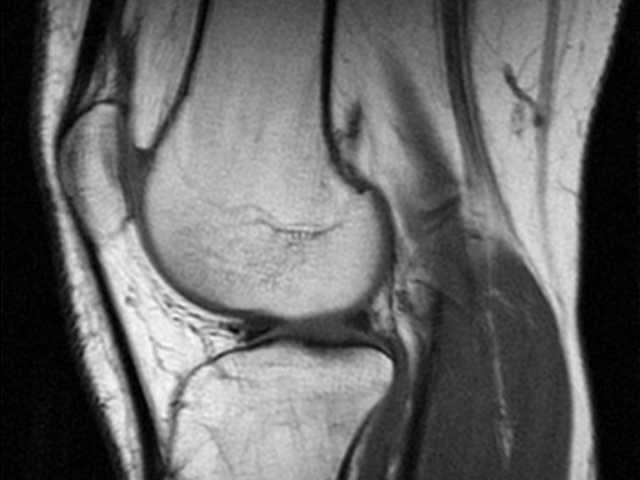

MRI検査は、体の中が見えすぎてしまうことが問題。

MRI検査の異常が痛みと関係するかどうかは、別の問題(医師の判断が重要になる)。

MRI検査でも異常が写りにくい体の場所がある。また、検査方法が良くないときも異常が出ません。

MRIの検査結果を生かすも殺すも、その情報処理をする医者次第。説明をする医師によって結果は違って来ます。